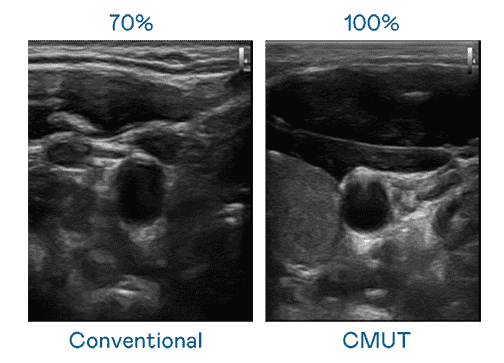

CMUT 技术是一种用电容式微机电元件来产生超音波讯号的技术。。与传统 PZT 压电式技术相比,,,,CMUT 频宽增加 30%,,更宽频的超音波讯号让影像解析度大幅提升,,是实现高影像品质医疗超音波扫描、、促进精准医疗发展的关键技术。。

超音波影像的解析度高低,,首先取决于探头能发出的讯号频宽。。。。至成国际 CMUT 可提供高清晰的超音波讯号,,,,提供高频宽、、高灵敏度、、影像纹理细节更高的超音波影像,,,协助医护人员缩短影像判读时间及利用精准的医疗影像进行诊断。。。